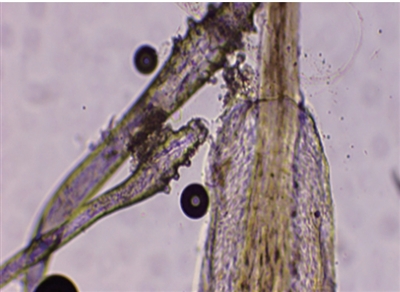

显微镜下,患者睫毛上的螨虫(白圈内)清晰可见。 医院供图

王女士就是其中一位。“眼睛反复发痒,一直以为是过敏,滴了眼药水也时好时坏,没想到竟是睫毛上长了螨虫!”王女士在浙江省人民医院眼科中心就诊时,看着检查屏幕上睫毛上密密麻麻附着的螨虫,既惊讶又困惑。